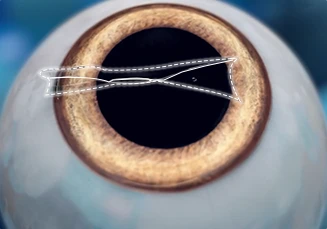

각막 주변부에 3mm 내외의

아주 작은 절개창을 만든다.

절개창을 통해

렌즈를 삽입한다.

기구를 이용해 렌즈를

홍채 뒤에 위치시킨다.